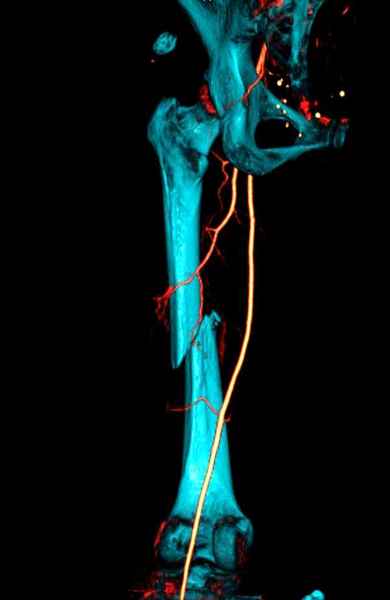

Для предупреждения кровотечения во время рассверливания, за день до операции провели эмболизацию сосудов питающий метастаз. http://radiology.rsnajnls.org/cgi/reprint/150/3/673.pdf (7-11, 12-15-16)